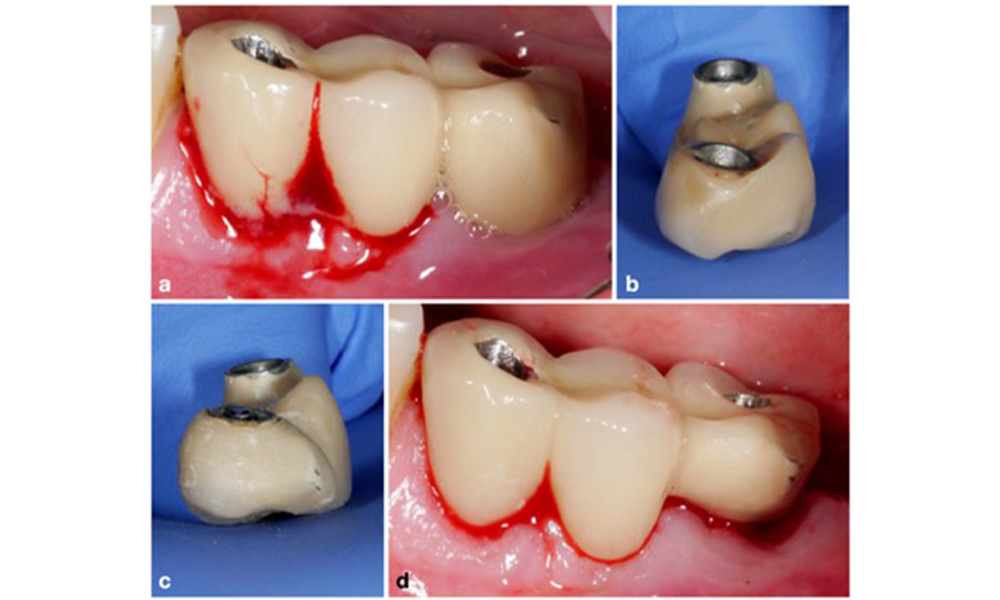

Periimplantitis ist zu erkennen an (1) Entzündungszeichen, vergleichbar einer Mukositis, (2) einem radiologischen Nachweis von Knochenverlust nach Ersteinheilung und (3) der Zunahme der Sondierungstiefe im Vergleich zu Messungen kurz nach dem Einsetzen der prothetischen Rekonstruktion (Abb. 2). Liegen keine früheren Röntgenaufnahmen vor, weisen ein radiologisches Knochenniveau von ≥ 3 mm zusammen mit Sondierungsblutungen und Sondierungstiefen von ≥ 6 mm auf eine Periimplantitis hin.

Restaurationen des gesamten Zahnbogens mit unterschiedlichem Grad der Periimplantitis bei einigen der Implantate. Das Implantat an Position 21 ist mit Sondierungstiefen von bis zu 9 mm (a), Sondierungsblutung, Eiterbildung am periimplantären Sulkus und einer vestibulären Fistel (b-c) stark betroffen. Die Röntgenaufnahme zeigt einen Knochenverlust von etwa 50 % für das Implantat mit Periimplantitis an Position 21, während das Implantat an Position 23 nur einen begrenzten Knochenverlust aufweist, entsprechend etwa dem, was bei Implantaten dieses Typs nach der Ersteinheilung zu erwarten ist (d).

Abb. 2. Restaurationen des gesamten Zahnbogens mit unterschiedlichem Grad der Periimplantitis bei einigen der Implantate. Das Implantat an Position 21 ist mit Sondierungstiefen von bis zu 9 mm (a), Sondierungsblutung, Eiterbildung am periimplantären Sulkus und einer vestibulären Fistel (b-c) stark betroffen. Die Röntgenaufnahme zeigt einen Knochenverlust von etwa 50 % für das Implantat mit Periimplantitis an Position 21, während das Implantat an Position 23 nur einen begrenzten Knochenverlust aufweist, entsprechend etwa dem, was bei Implantaten dieses Typs nach der Ersteinheilung zu erwarten ist (d).

Der erwartete Knochenverlust nach Ersteinheilung ist auf die marginale Knochen-Remodellierung zurückzuführen und variiert in Abhängigkeit von Faktoren wie Implantatsystem oder Implantattyp.

Ein Knochenverlust von 1–2 mm gilt beispielsweise bei Implantaten auf Knochenniveau mit Außenverbindung allgemein als „normal“ (Abb. 2d, Implantat an Position 23).